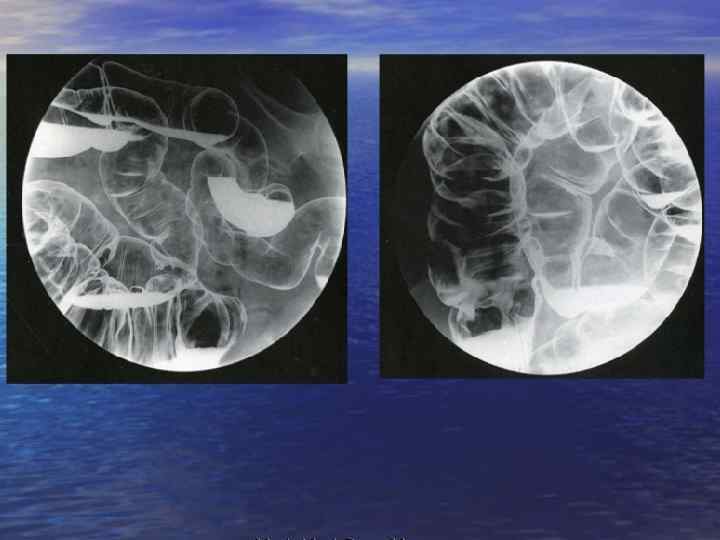

ПРИМЕНЕНИЕ Препараты бария сульфат В течение полувека применяются для контрастирования ЖКТ, их главное достоинство — фармакологическая инертность, однако они неприменимы для контрастирования закрытых полостей или сосудистых образований. Органические йодсодержащие РКС Применяются для ангиографии, урографии, коронарографии, холецистографии, миелографии и других разновидностей этих методов.